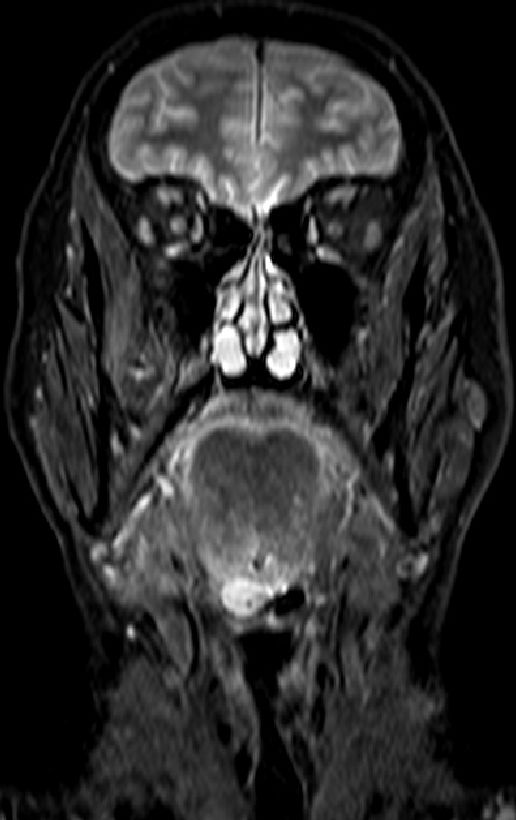

Klinik Großes Zungenrand-Karzinom mit überschreiten der Mittellinie, Befall der Tonsille rechts.

Diagnostik Zunächst CUP mit Lymphknotenpaket links Level III. Im MRT Zungengrundtumor nahe der Mittellinie.